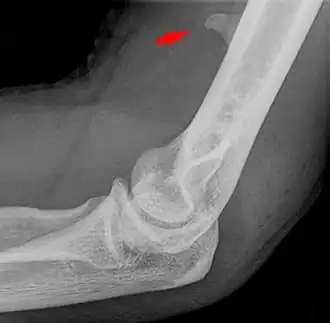

![]() Larger supracondylar process seen on a lateral radiograph of the elbow | |

The supracondylar process of the humerus (also known as an avian spur) is a variant bony projection on the anteromedial aspect of the upper arm bone (humerus), about 5–6 cm above the medial epicondyle.[1] It is directed downward, forward and medially pointing to the medial epicondyle. A fibrous band, Struthers ligament, may connect this process to the medial epicondyle.[2] This variation has a prevalence of 0.68% and is significantly more common in women than in men.[3]

Supracondylar processes are usually asymptomatic, but may be palpable as a mass on the upper arm. They are most commonly found as an incidental finding on radiographs made for other reasons, but occasionally isolated fractures of the process itself may lead to its discovery. Rarely, presence of the process and a connecting ligament may lead to compression of the brachial artery and the median nerve,[4] leading to pain, paresthesia,[2] and/or ischemia.